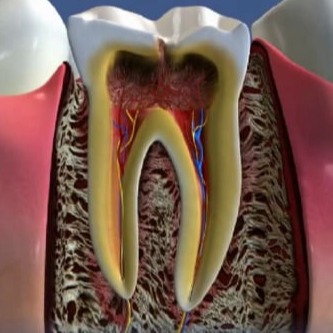

2. Κλινική εξέταση: Ο οδοντίατρος εξετάζει τα δόντια, τα γένεθλια, τη γλώσσα, τα χείλη και τα άλλα μέρη του στόματος για τυχόν προβλήματα όπως τερηδόντωση, καριές, περιοδοντική νόσο, κακοστομία και άλλα.

Ακτινογραφίες: Οι ακτινογραφίες, όπως οι πανοραμικές ακτινογραφίες και οι ακτινογραφίες με ροϊάντ, μπορούν να βοηθήσουν στη διάγνωση προβλημάτων που δεν είναι ορατά με το μάτι.

Διάγνωση και συστάσεις: Με βάση τις ευρήματα της εξέτασης, ο οδοντίατρος καθορίζει τη διάγνωση και προτείνει τον κατάλληλο σχεδιασμό θεραπείας.